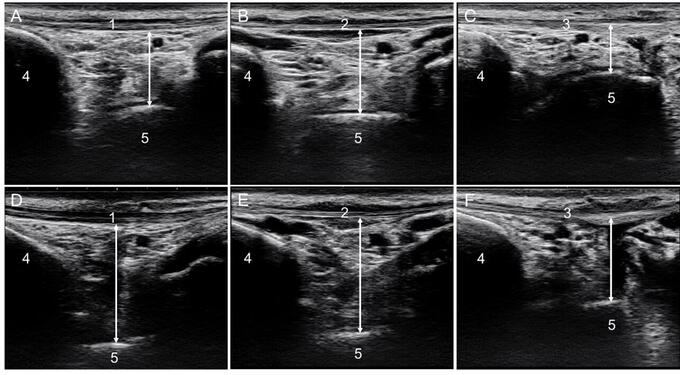

図 超音波画像(Bモード)

1:前脛骨筋腱、2:長母指屈筋腱、3:長趾伸筋腱、4:脛骨、5:距骨